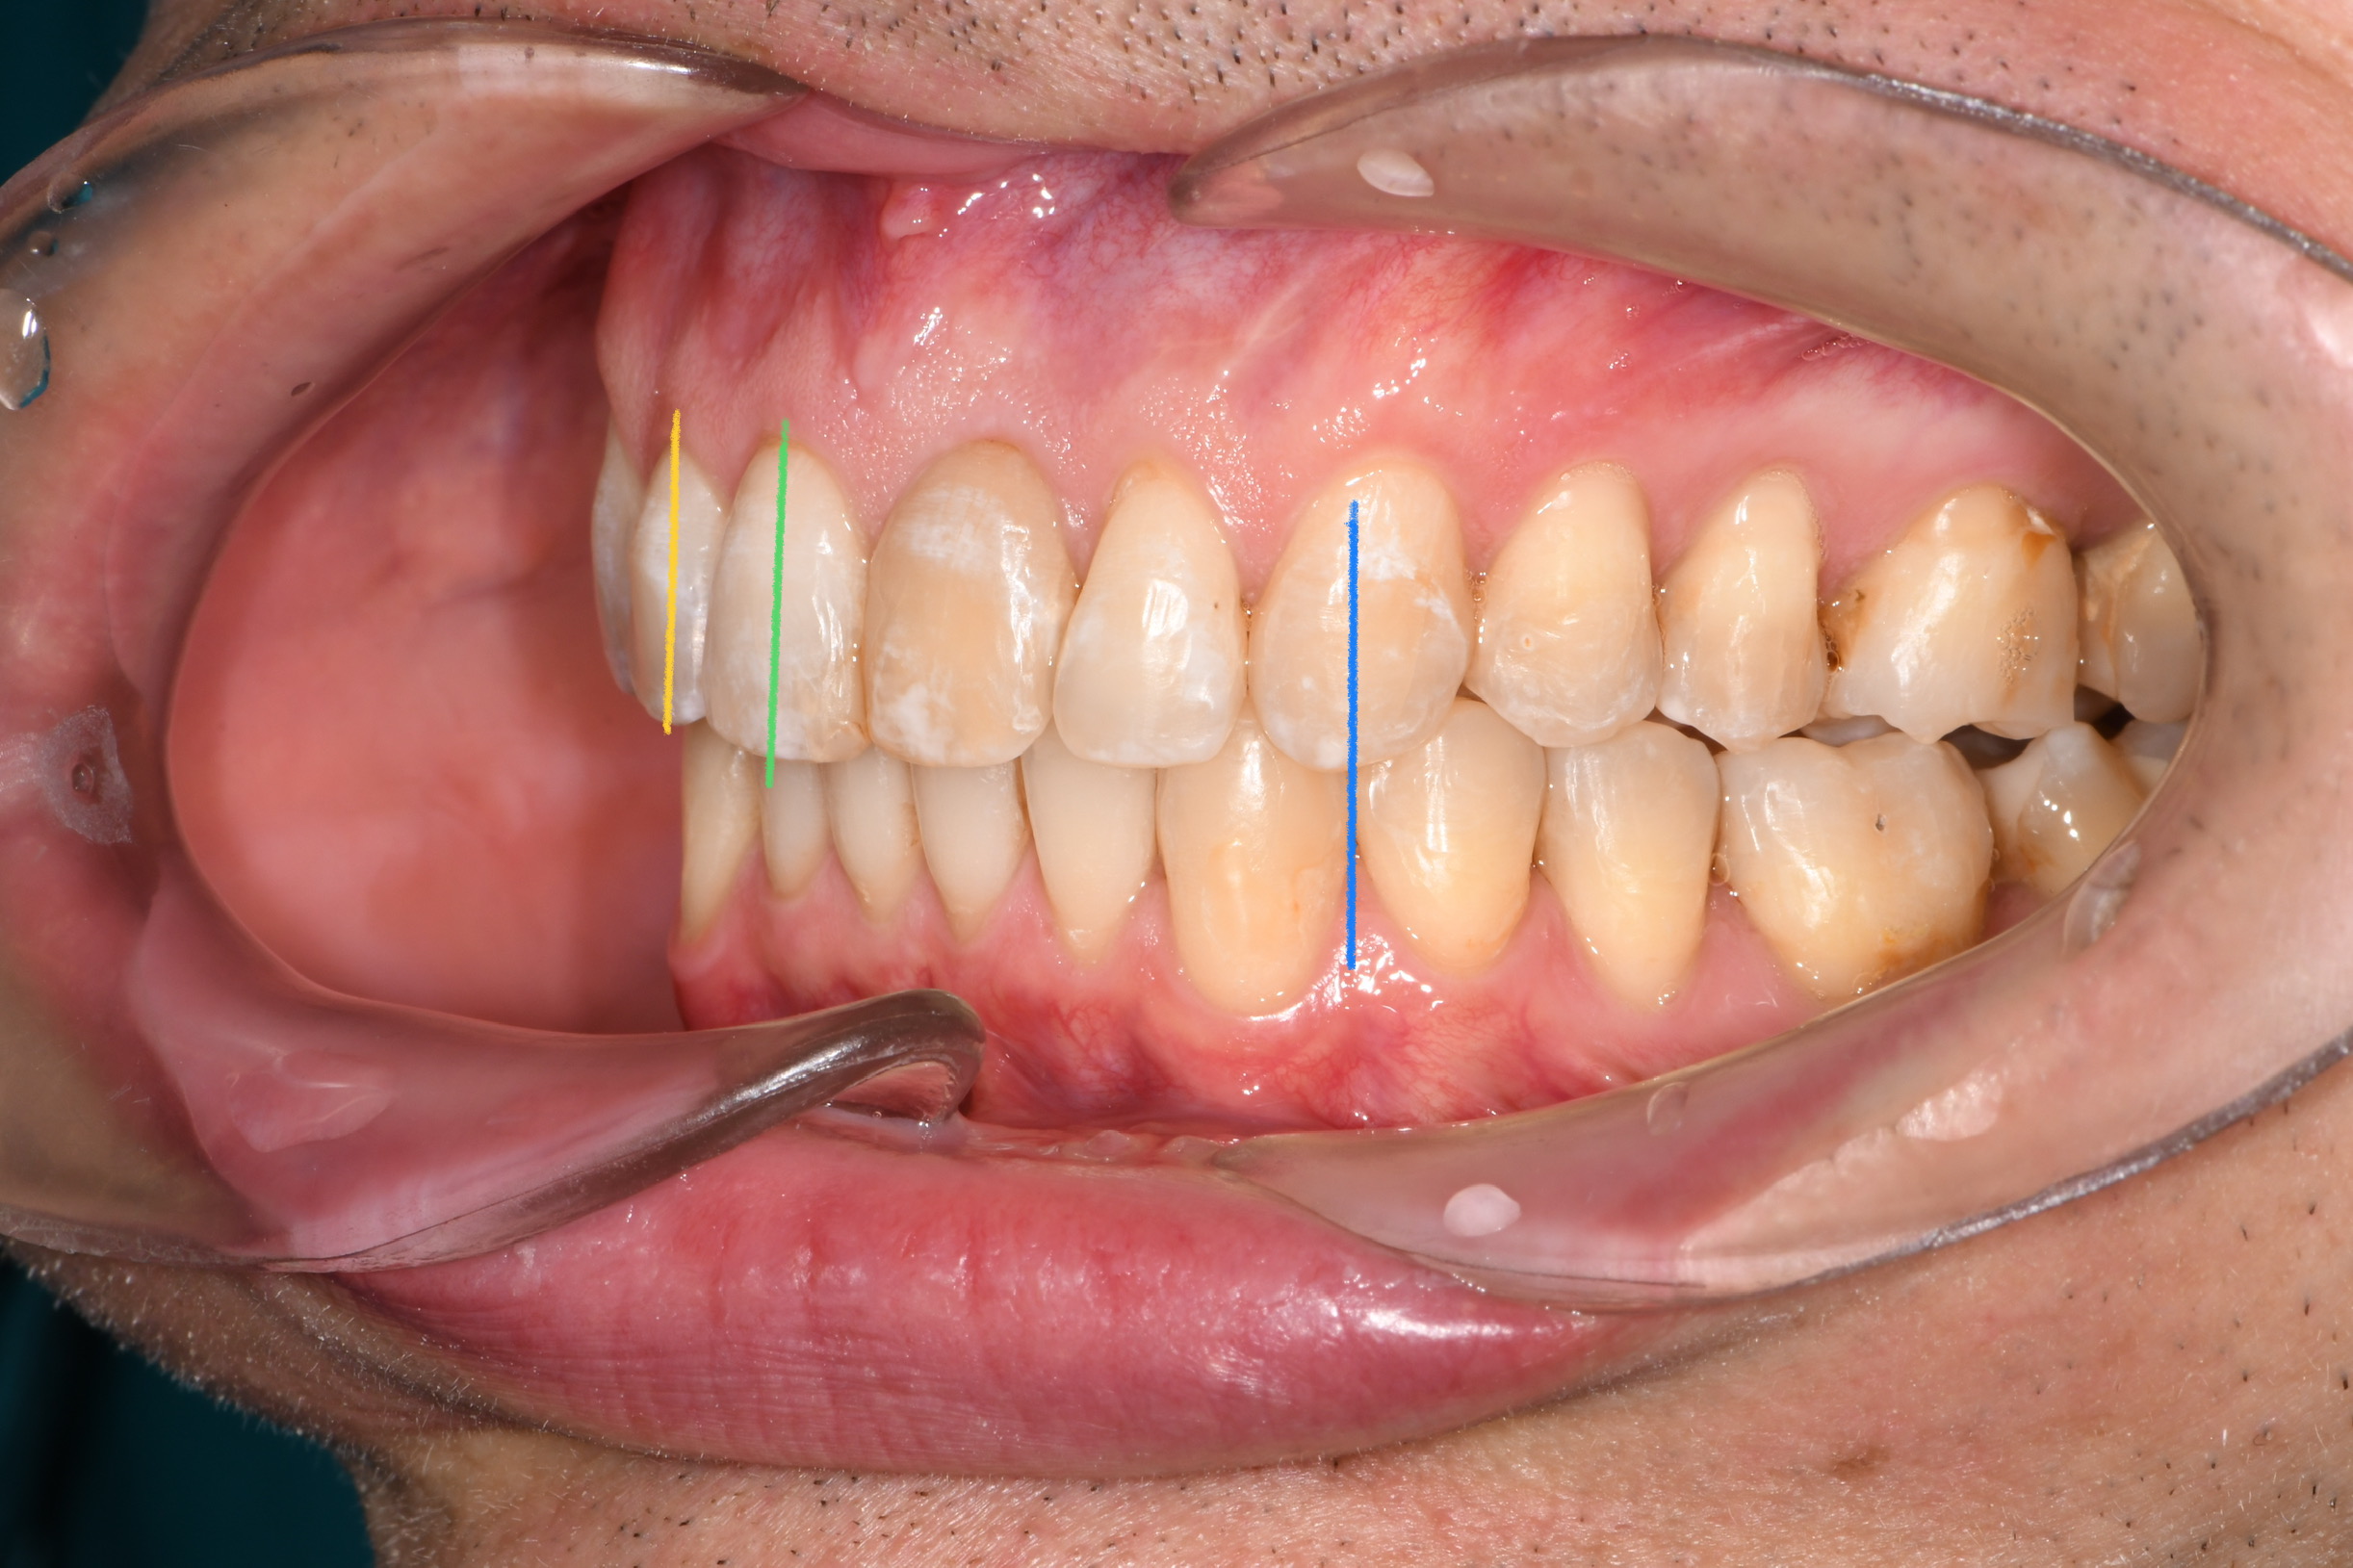

Az elmúlt évekből rengeteg szakmai referenciát tudnánk bemutatni, amelyek különböző fogszabályozási problémákat oldottak meg. Válogatva a több száz esetből, ezen az oldalon olyan képeket, információkat igyekeztünk bemutatni, amelyeknek a segítségével a jövőbeni pácienseinknek azt tudjuk üzenni: A Te fogsorod is lehet gyönyörű!

(Képeket a Pácienseink külön írásos beleegyezésével mutatjuk be!)